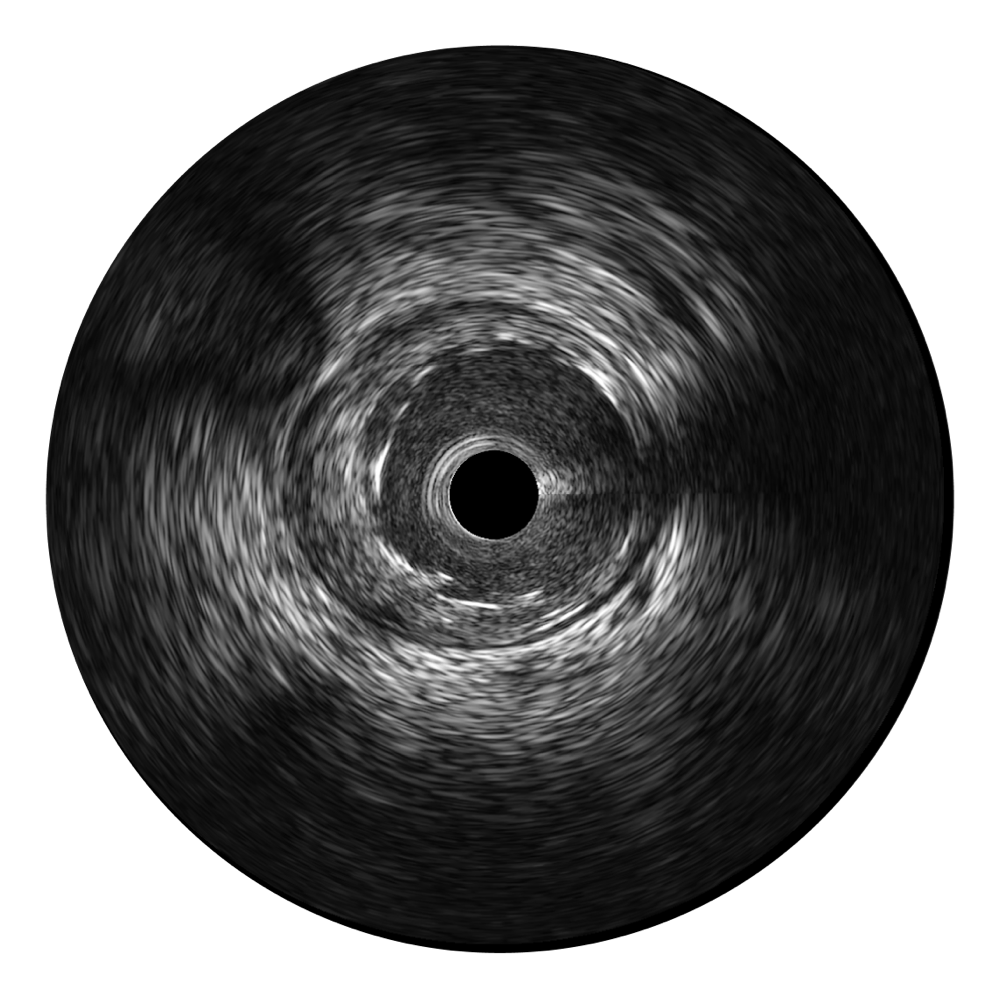

• 乐玩lewin国际宽频IVUS图像

• 传统IVUS图像

对比传统IVUS导管成像,乐玩lewin国际宽频IVUS图像的近场支架梁显影更细腻,远场中膜外血管仍清晰可辨,兼顾远中近,兼顾分辨力与穿透深度